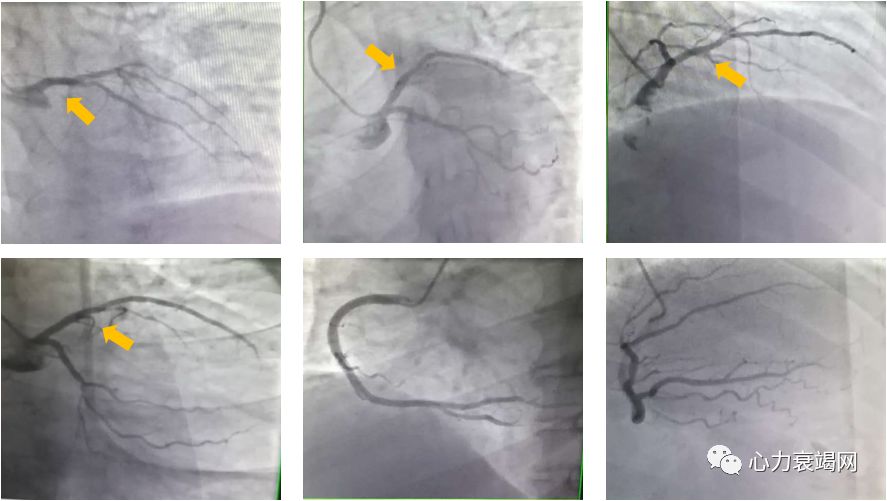

➤ 冠状动脉造影

左冠状动脉前降支近段:全程弥漫偏心不规则100%狭窄局部桥状侧支(完全闭塞>3个月),远端管腔差,病变属于原发病变。

左冠状动脉前降支中段:近段弥漫偏心不规则100%狭窄局部桥状侧支(完全闭塞>3个月),远端管腔差,病变属于原发病变。

诊断:单支病变,累及前降支。